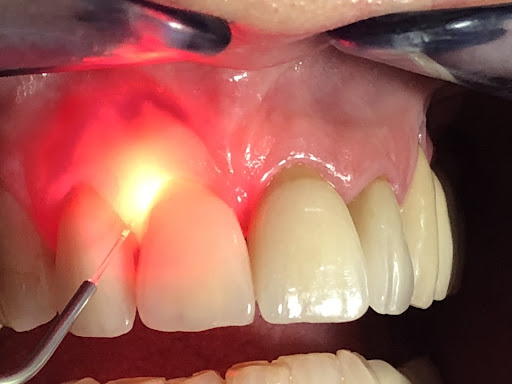

Benefits of Laser Gum Therapy

Laser gum treatment is gaining popularity in Kukatpally due to its many benefits:Why Choose Q Dental Clinic in Kukatpally?